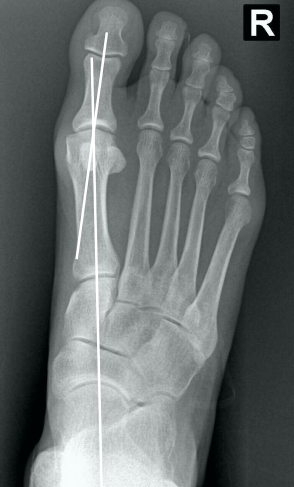

• Na radiografia em AP com carga, como é traçado o ângulo de valgismo interfalângico do hálux?

• Ângulo entre o eixo longo da falange proximal e o eixo longo da falange distal

• Normal → até 10°

19

• Na radiografia em AP com carga, como é traçado o ângulo articular metatarsal distal (AAMD)?

• Traça-se uma linha unindo os dois pontos mais largos da superfície articular do 1° mtt e outra linha perpendicular a esta

• Depois, traça-se uma linha no eixo longo do 1° mtt

• O ângulo entre as duas maiores retas → até 15°